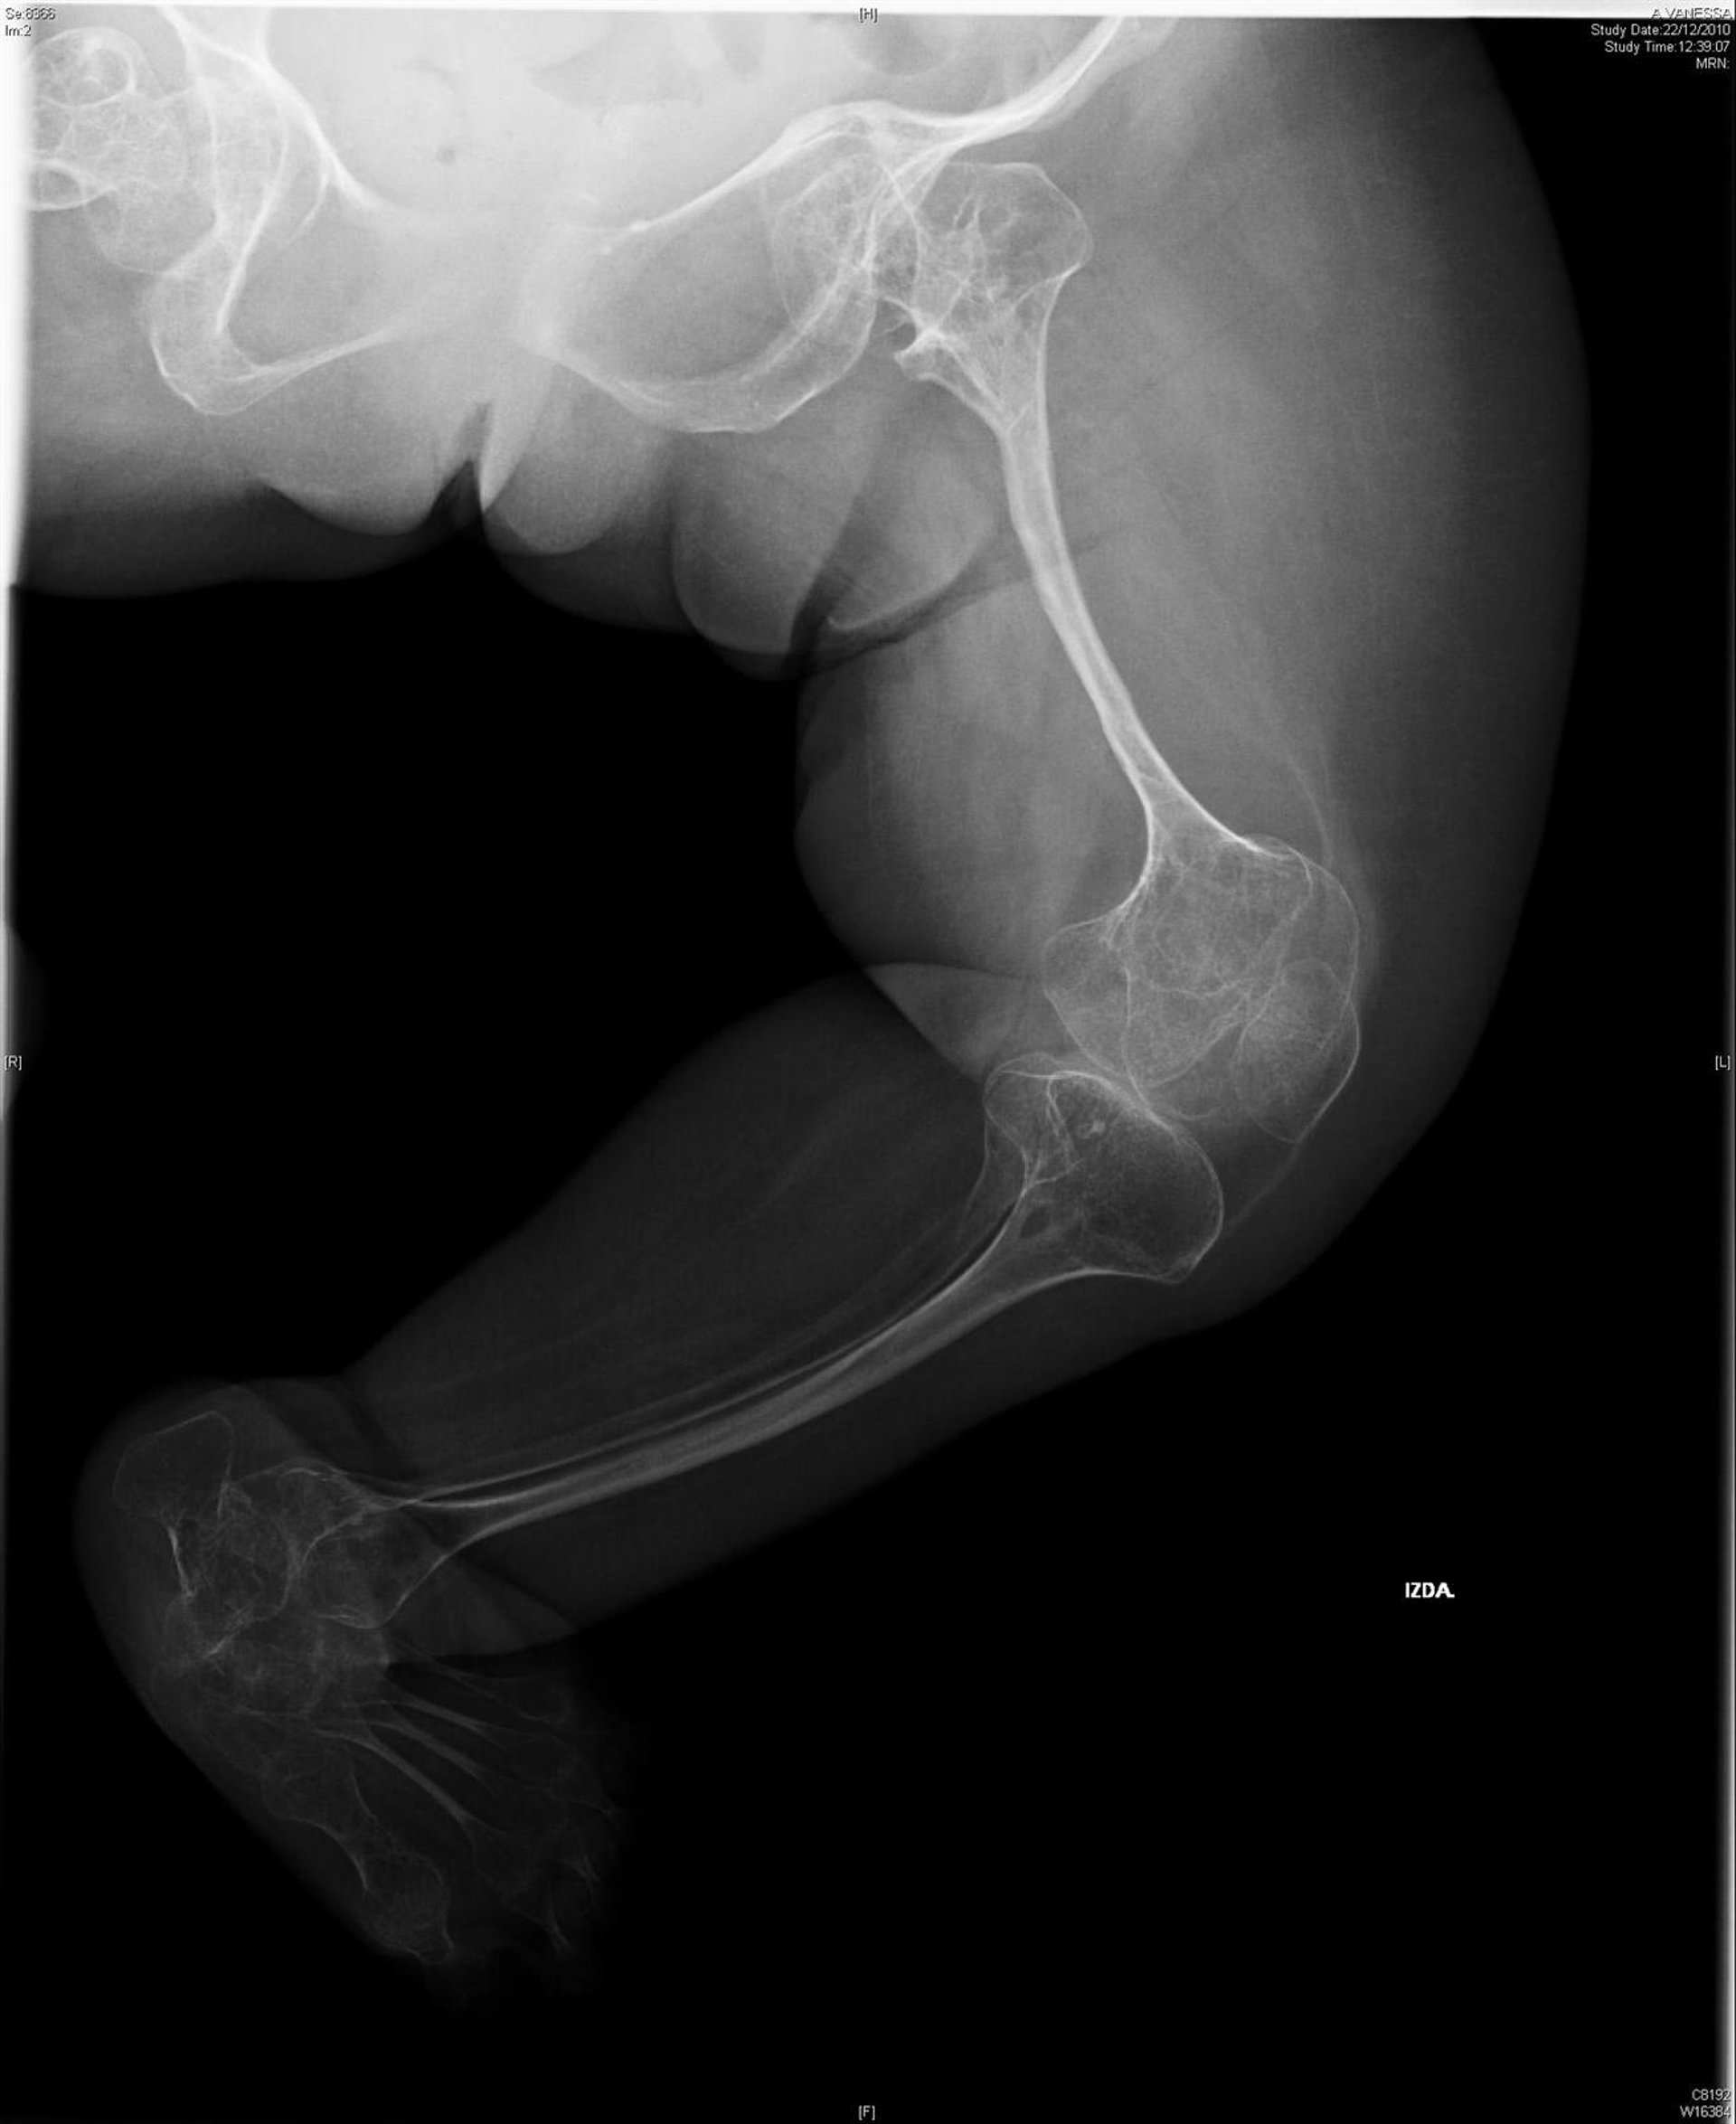

También conocida como la enfermedad de los huesos de cristal, la osteogénesis imperfecta se caracteriza por la susceptibilidad a fracturas óseas. Esta patología rara es genéticamente heterogénea y ya se conocen unos 20 genes que la pueden causar.